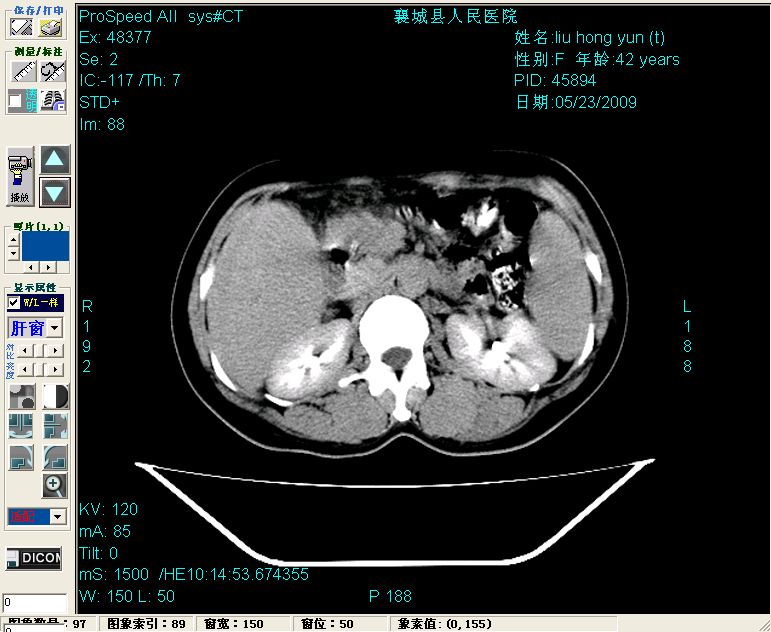

增强:

增强动脉期前述低密度区轻度早其强化,门脉期强化程度显著增高,延期扫描强化程度下降,但仍为相对高密度影

1)肝内胆管结石,胆总管末端结石伴肝内胆管扩张。2)肝左叶及肝右叶前段增强前后之异常表现,考虑炎性改变,不排除胆管细胞癌。

1)肝内胆管结石,胆总管末端结石伴肝内胆管扩张。2)肝左叶及肝右叶前段增强前后之异常表现,考虑炎性改变,不排除胆管细胞癌。3)脾大。